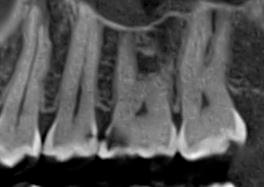

Ми розуміємо, наскільки важлива деталізація в ендодонтії та терапевтичному лікуванні.

Завдяки флагманському обладнанню PLANMECA, ми отримуємо знімки з мінімальним рівнем шумів та

високою роздільною здатністю, що дозволяє чітко візуалізувати морфологію кореневих каналів,

приховані каріозні порожнини та стан періапікальних тканин.